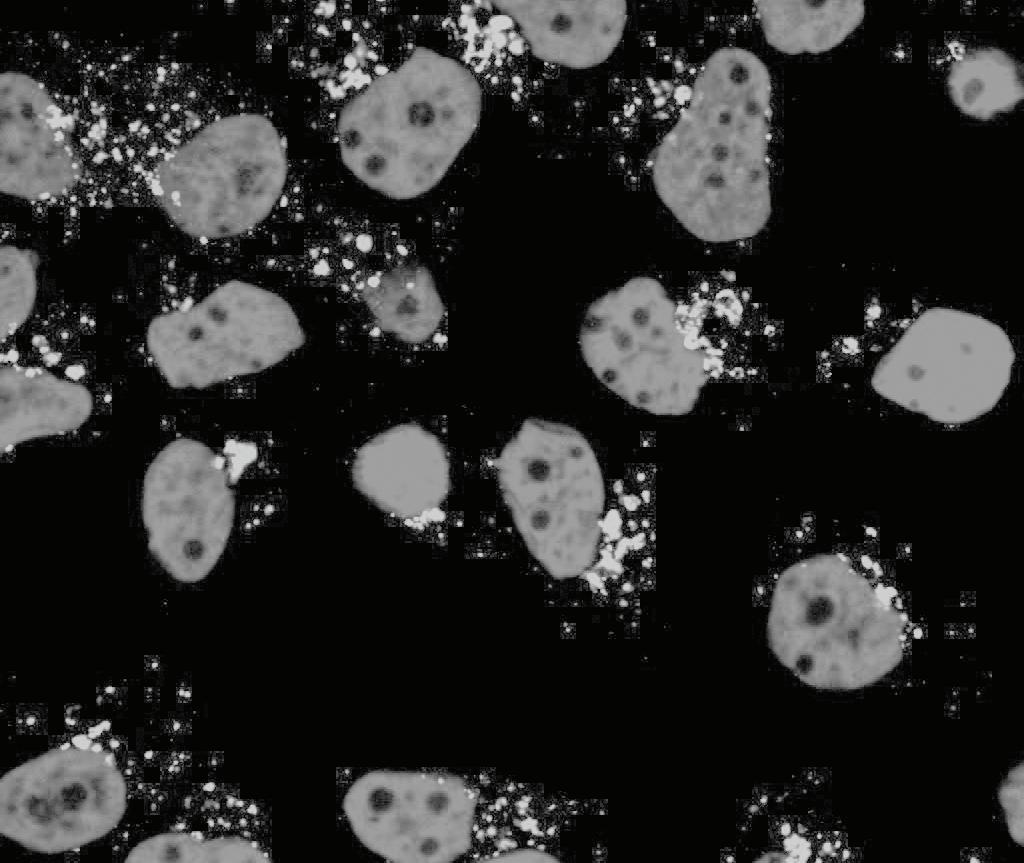

A pesar de que las terapias contra el cáncer han evolucionado, aún queda el desafío de lograr tratamientos más efectivos. El principal problema de las terapias tradicionales es su toxicidad y el desarrollo de resistencia por parte de las células tumorales. Contamos con un gran número de terapias dirigidas, sin embargo, en muchos casos, las mismas apuntan contra lo que se denomina el “bulto” tumoral, sin eliminar a una pequeña población de células denominadas “madre” o iniciadoras de tumor. Estas son las responsables del desarrollo de metástasis y recurrencias. En este contexto, la nanotecnología se presenta como una herramienta prometedora para delinear nuevas estrategias terapéuticas, ya que permite, por sus características, dirigirse a varios blancos en simultáneo. En el área de nanomedicina del INS trabajamos de manera interdisciplinaria en el diseño de nanopartículas multifuncionales basados en dos ejes: 1) expertise en el diseño y síntesis de nanopartículas multifuncionales; 2) sólidos conocimientos de los mecanismos implicados en la progresión tumoral. El objetivo final de este equipo de trabajo es el desarrollo de terapias que se dirijan exclusivamente al tumor, disminuyendo la toxicidad sistémica, y que eliminen a las células responsables de la recurrencia tumoral.

Although cancer therapies have evolved in the last 50 years, still today, as researchers, we face the challenge of achieving more effective treatments for this family of diseases. The main problem of traditional therapies is their toxicity and the development of resistance. Even though most therapies are targeted to specific tumor cell pathways, many are effective against the tumor bulk, but do not eliminate infiltrating immune cells or cancer stem cells that are key players in progression and recurrence. In this context, nanotechnology is a promising tool to delineate new therapeutic strategies, since it allows to tackle several targets simultaneously. In the Nanobiology laboratory of the INS we work interdisciplinary in the design of multifunctional nanoparticles based on two axes: 1) expertise in the design and synthesis of multifunctional nanoparticles; 2) solid knowledge of the mechanisms involved in tumor progression. The goal of this team is the development of therapies that target different key players within the tumor, decreasing systemic toxicity, and eliminating the cells responsible for tumor progression and recurrence.